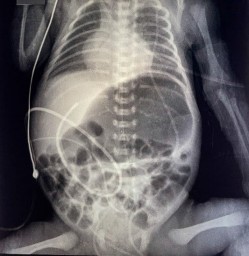

El paciente cursó desde las 12 horas de vida con vómitos lácteos (10-15cc) tras el inicio de la nutrición enteral (20cc/kg/día), que estuvo acompañada por distensión abdominal intermitente y residuos gástricos biliosos de cuantía 2-11cc. El paciente realizaba deposiciones de manera espontánea con una frecuencia de 1 vez cada 5 días. Se indicó reposo gástrico y al reinicio de vía oral presentó la sintomatología digestiva ya descrita, motivo por el cual fue sometido a estudios de laboratorio y de imágenes (Tabla 1). En la evaluación física general se evidenció abdomen globuloso con episodios de distensión abdominal intermitente, con ruidos hidroaéreos presentes pero disminuidos y poco depresible a la palpación; el resto del examen físico no mostró alteraciones. El paciente fue evaluado por Cirugía Pediátrica, sin evidencia de irritación peritoneal; no tributario de tratamiento quirúrgico, por lo que se solicitó complementar con un estudio de imagenología. Se realizaron radiografías simples de abdomen en decúbito y de pie, y se evidenció signo de doble burbuja (Figura 1).

Figura 1 Evidencia de signo de doble burbuja, resultado de distensión de la cámara gástrica y del duodeno proximal

| 10/09/2021 | Se solicita radiografía de abdomen: signo de “doble burbuja”. |

El diagnóstico generalmente se realiza por la presencia de una doble burbuja de aire (en una radiografía simple de abdomen), pero puede confirmarse mediante una serie gastrointestinal superior que demuestre obstrucción duodenal 8. Pero no representa el diagnóstico definitivo debido a que puede verse en otras afecciones, como la atresia duodenal y la malrotación intestinal 15. Los hallazgos en la serie gastrointestinal superior incluyen un estrechamiento duodenal con un estrechamiento excéntrico o concéntrico de la segunda porción del duodeno, y dilatación simétrica del duodeno proximal 4. Sin embargo, no se requieren pruebas adicionales debido a que la sospecha de obstrucción duodenal completa o parcial requieren intervención quirúrgica 15. Por lo tanto, se realiza un diagnóstico definitivo en la laparotomía 8. En el caso de nuestro paciente fue necesario complementar el estudio con la serie gastrointestinal superior con contraste, en la que se evidenció la dilatación de la porción superior y descendente del duodeno, junto a la estenosis duodenal distal. Este fue el motivo por el cual se ingresó a laparotomía exploratoria en su décimo primer día de vida.

El caso presentado comenzó a dar manifestaciones de distensión abdominal y vómitos en el primer día de vida, tal y como se describen los casos en etapa neonatal en la literatura. Se corroboró el diagnóstico con el examen radiográfico de pie, con la imagen típica de "doble burbuja" 15, sumado a la estrechez duodenal evidenciada mediante la serie gastrointestinal superior con contraste. Lo anterior concuerda con la literatura respecto a la limitación diagnóstica que tiene el páncreas anular 14; sin embargo, el diagnóstico definitivo y terapéutico es la intervención quirúrgica 13. Durante el acto quirúrgico se identificó que la obstrucción intestinal era ocasionada por una estenosis duodenal secundaria a páncreas anular, por lo cual se procedió a realizar la técnica quirúrgica de elección (cirugía de Kimura) sin presentar complicaciones inmediatas.